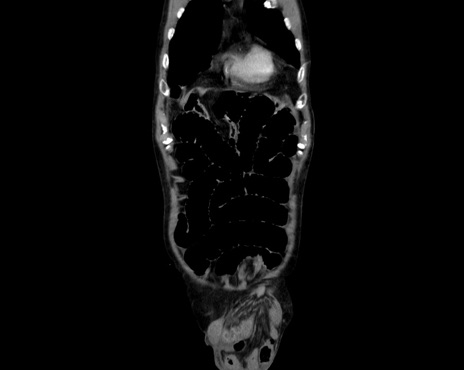

横断像